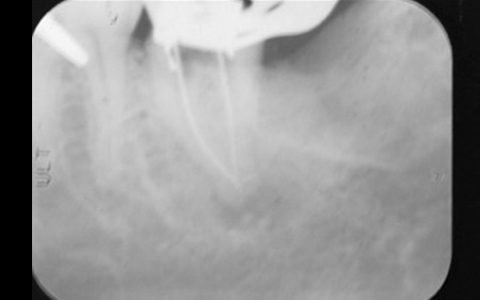

さらに再根管治療をしている歯のCTを撮影すると、歯根が破折していないにも関わらず、CTでは歯根が破折しているように見えることがあり、実は私達が見ているレントゲン(CTも含めて)は、その画像だけでは正しく診断できません。

通常のレントゲンは平面による撮影のため情報量少なく正確な診断が難しいですが、歯科用CTは三次元の立体的な画像で確認することができるため、神経の位置や根管内もしっかりと確認できます。

精密な治療をご提供するために、歯科用CTによる正確な画像診断を行うことがあります。

根管の数が1つに見えても、マイクロスコープで見ると実際にはもう1つ根管が隠れていることも多く、根管が見逃されているケースが多々あります。

マイクロスコープを使用することで、複雑な歯の中を12~20倍に拡大して見ることができ、根管を見逃すことなく精密な治療が可能となります。